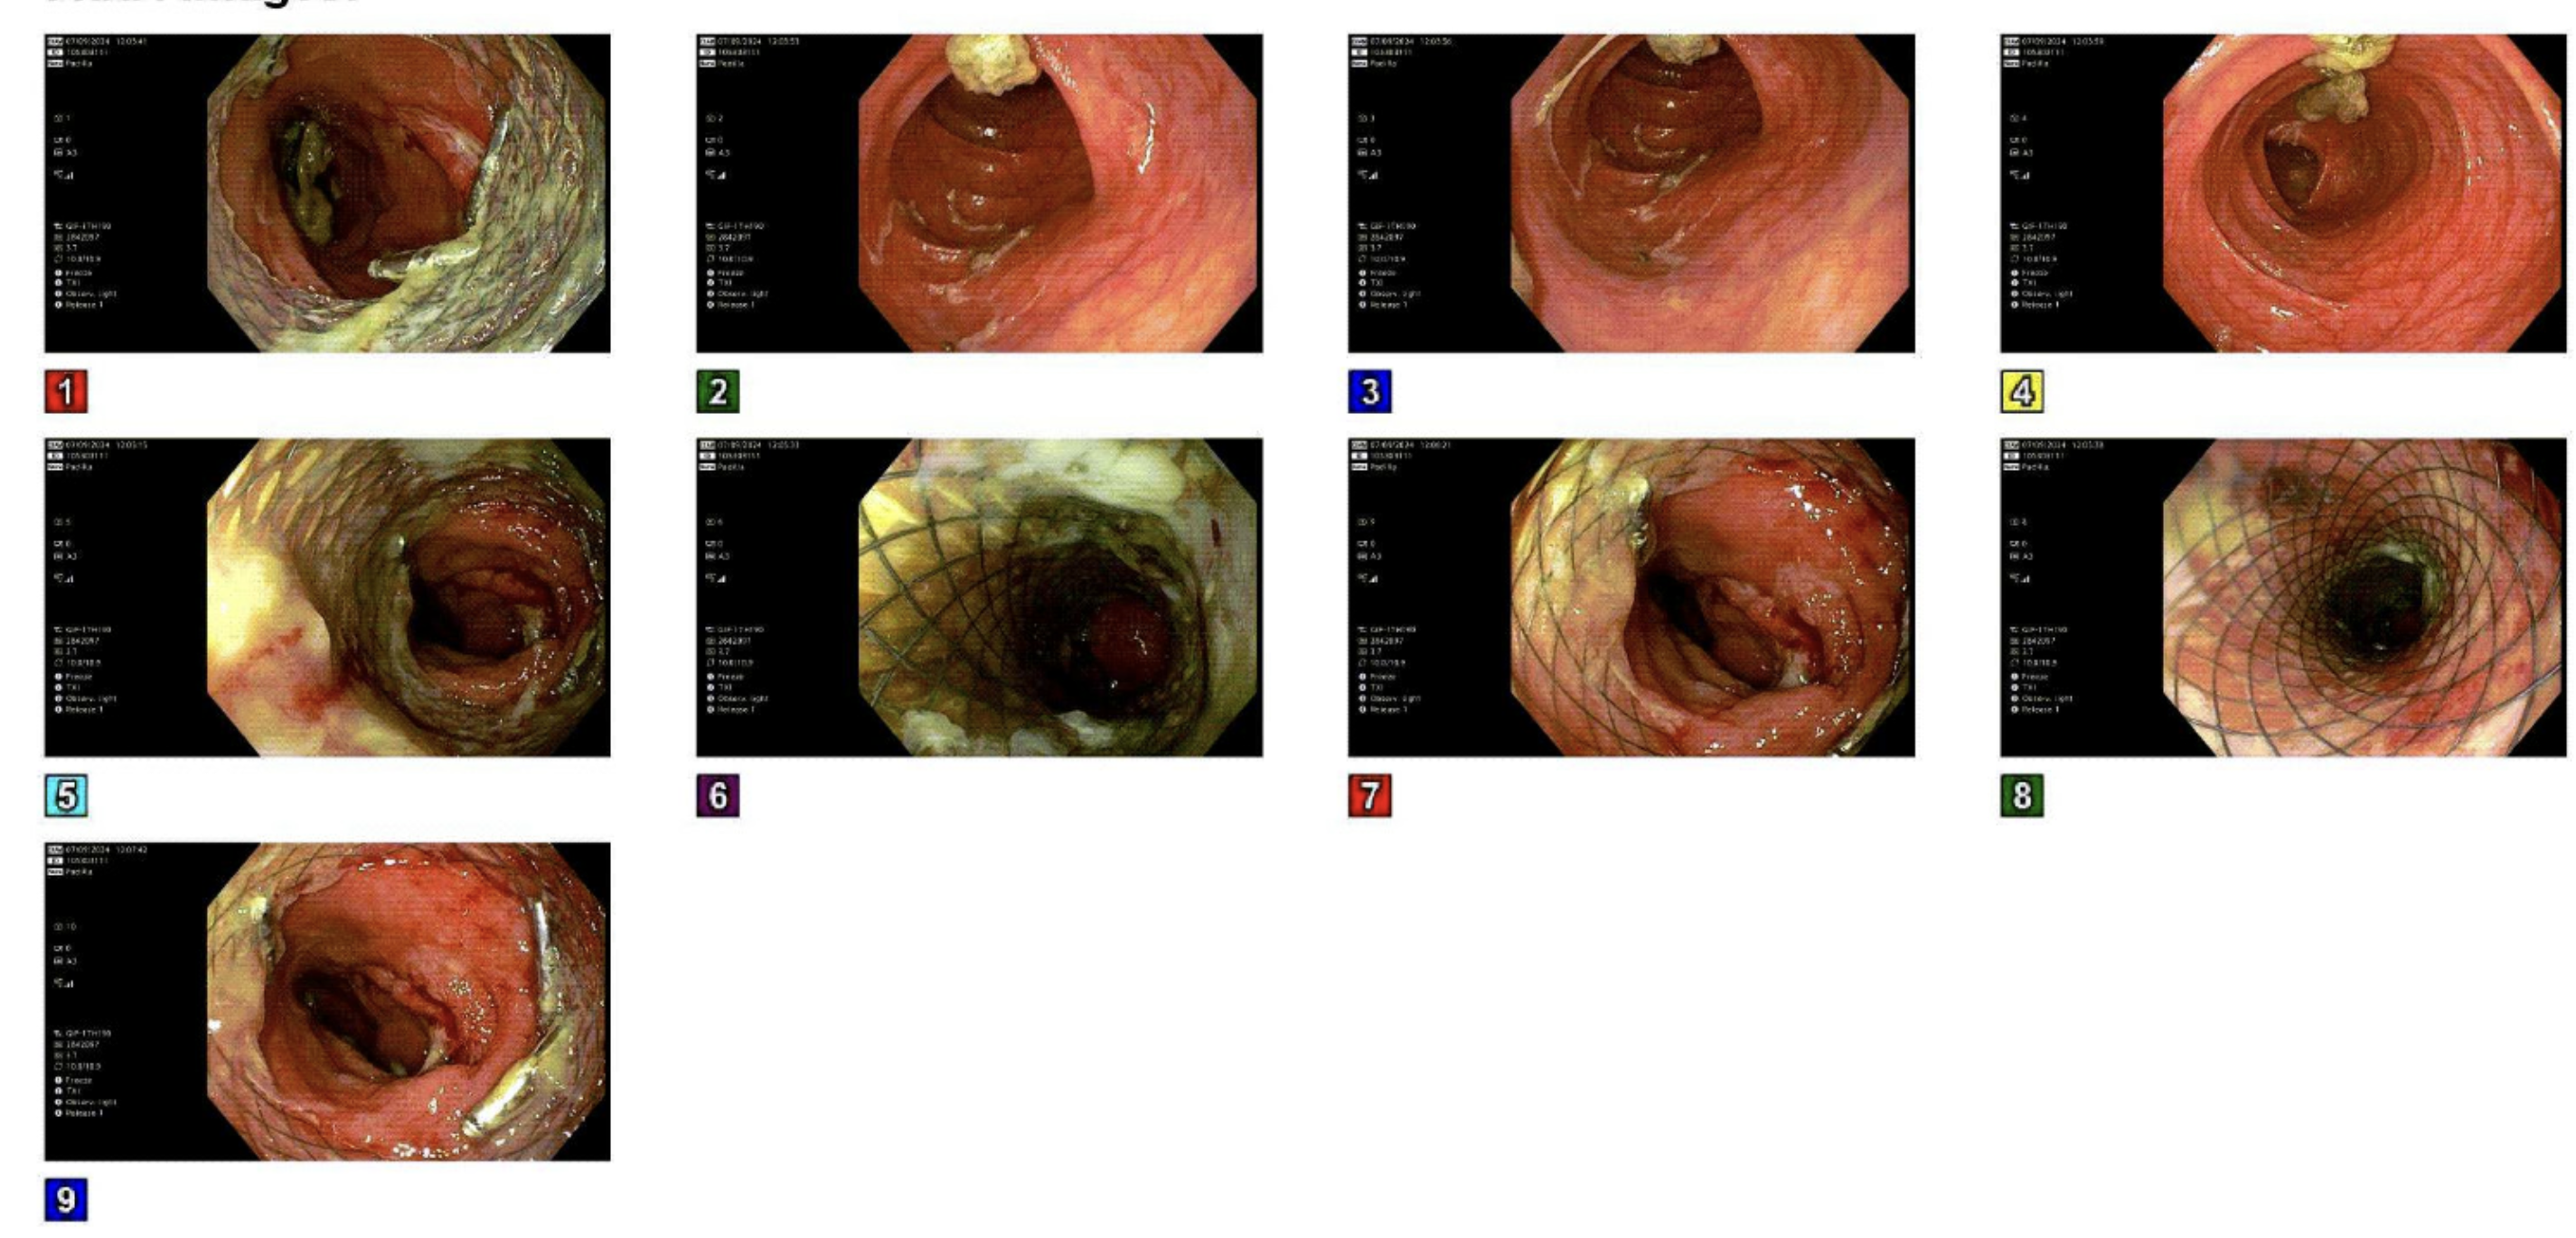

Visualized well deployed and expanded stent with widely patent sigmoid lumen, 1 month post procedure